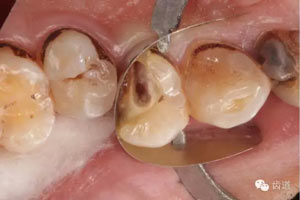

檢查:14遠(yuǎn)中鄰頜面探及齲壞至牙本質(zhì)深 層,穿髓。探-,冷-,叩-。松動(dòng)-。牙齦無(wú)紅腫,未探及牙周袋。

處理:去齲,擴(kuò)大穿髓孔,揭髓室頂,根管探查,探及頰腭兩根管口,去除牙本質(zhì)肩領(lǐng),根管疏通:k file10#至15#。確定wl。鎳鈦器械M Two根管預(yù)備至2506。根管預(yù)備中大量使用1%次氯酸鈉和17%edta溶液。預(yù)備結(jié)束后生理鹽水結(jié)合超聲蕩洗,干燥根管,根管內(nèi)放置氫氧化鈣糊劑,Zoe暫封。